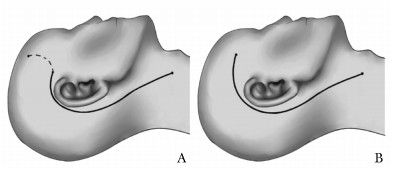

方法  回顾性分析2015年8月至2021年1月北京协和医院诊治的累及颈静脉孔区的侧颅底副神经节瘤患者临床资料。根据肿瘤与面神经的关系,术中对面神经进行不同方式的处理。对不同处理方式患者的术后面神经功能进行总结。

结果  共纳入30例累及颈静脉孔区的侧颅底副神经节瘤患者。Fisch分型为C1型3例,C2型6例,C2De1型2例,C2Di1型2例,C3De1型7例,C3Di1型5例,C3Di2型3例,C4De1型1例,C4Di1型1例。术前面神经功能House-Brackmann(HB)分级Ⅰ~Ⅱ级22例,Ⅲ级2例,Ⅳ级3例,Ⅴ级2例,Ⅵ级1例。经术后MRI检查证实,30例患者肿瘤均彻底切除。术后中位随访886 d,均未见复发。肿瘤未触及面神经15例,术中均行面神经前移,其中术后HB分级Ⅰ~Ⅱ级13例,Ⅲ级2例。肿瘤部分粘连面神经2例,术中均成功将面神经与肿瘤分离,其中术后HB分级Ⅰ~Ⅱ级1例,Ⅲ级1例。肿瘤包绕面神经13例,其中1例术中将面神经与肿瘤分离,术后HB分级Ⅲ级;余12例术中均未能将面神经与肿瘤分离,其中3例同期或分期行面神经重建,术后HB分级Ⅰ~Ⅱ级1例,Ⅲ级2例,余9例未行面神经重建,术后HB分级均为Ⅵ级。

Methods  We retrospectively analyzed the clinical data of patients with lateral skull base paraganglioma involving jugular foramen that were diagnosed and treated in Peking Union Medical College Hospital from August 2015 to January 2021. According to the relationship between the tumor and the facial nerve, the facial nerve was treated in different ways during the operation. The postoperative facial nerve function of patients with different treatments is summarized.

Results  A total of 30 patients with lateral skull base paraganglioma in the jugular foramen area were included. The Fisch classification of these patients was as followed: C1(n=3), C2(n=6), C2De1(n=2), C2Di1(n=2), C3De1(n=7), C3Di1(n=5), C3Di2(n=3), C4De1(n=1), C4Di1(n=1). Preoperative facial nerve function assessed by House-Brackmann (HB) grade: grade Ⅰ-Ⅱ (n=22), grade Ⅲ (n=2), grade Ⅳ (n=3), grade Ⅴ(n=2), grade Ⅵ(n=1). All tumors were completely resected, which was verified by post-operational MRI. No recurrence was observed during the medium follow-up of 886 days. All of the postoperative nerve function refers to the results of the last follow-up. Anterior facial nerve rerouting was performed in 15 cases whose tumor did not invade the facial nerve. The postoperative facial nerve function was HB grade Ⅰ-Ⅱ in 13 cases and HB grade Ⅲ in 2 cases. The tumors were adhesive to the facial nerve in 2 cases. The tumors and the facial nerve were successfully separated in both cases; one achieved HB grade Ⅰ-Ⅱ, while the other was HB grade Ⅰ-Ⅱ postoperatively. In 13 cases, the tumor wrapped the facial nerve. Among those patients, the tumor was separated from the facial nerve in 1 case, with the postoperative facial nerve function of HB grade Ⅲ. In the remaining 12 cases, the facial nerve was resected together with the tumor. Facial nerve reconstruction was performed in 3 cases in the same or the second surgery. The postoperative facial nerve function was HB gradeⅠ-Ⅱ in 1 case and HB grade Ⅲ in the other 2 cases. The postoperative facial nerve function in the remaining 9 cases that did not receive facial nerve reconstruction was HB grade Ⅵ.

Conclusions  In patients with lateral skull base paraganglioma, anterior facial nerve rerouting has a slight effect on the function of facial nerve, if the tumor does not invade the facial nerve. It is difficult to separate the tumor and the facial nerve, if the facial nerve is wrapped by the tumor, and the rate of postoperative facial nerve paralysis is higher in these cases.